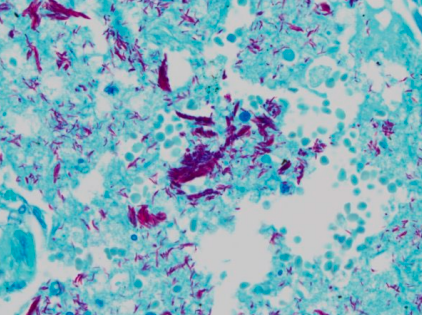

Product for the preparation of cyto-histological samples for optical microscopy. To show pathogenic mycobacteria (especially Koch’s bacillus) in sputum smears and culture smears.

Acid resistance is a particular dyeing feature of mycobacteria. Once they have been stained with carbol fuchsin, they have the capacity to remain red even if they undergo strong decolourizations. Acid resistance is usually ascribed to the special composition of mycobacteria’s cell walls, which are very rich in lipids.